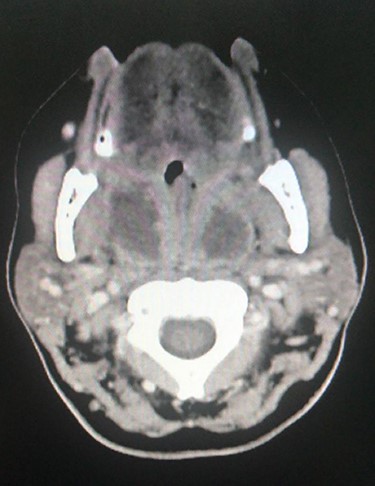

CT scan with IV contrast, axial view showing bilateral peritonsillar abscess with rim enhancement.

Examination revealed that the patient appeared sick, pale, with a muffled voice known as hot potato voice, mild trismus with limited mouth opening, with no stridor or respiratory distress, bilateral lateral neck lymph node enlargement, fever, enlarged peritonsillar spaces and bilateral tonsils with exudates and uvula pushed anteriorly, posterior pharyngeal wall not visualized and a narrow airway. Her oxygen saturation from room air was over 95%, temperature 37.8°C, heart rate 138 beats/min, WBCs 9.59, C-reactive protein 270 and erythrocyte sedimentation rate 55. A computerized tomography of her neck with intravenous contrast showed bilateral hypodense peripheral enhanced cavities filled with fluids in the peritonsillar spaces, with left multilocular appearance (Fig. 1). Bilateral cervical lymph nodes were noted.